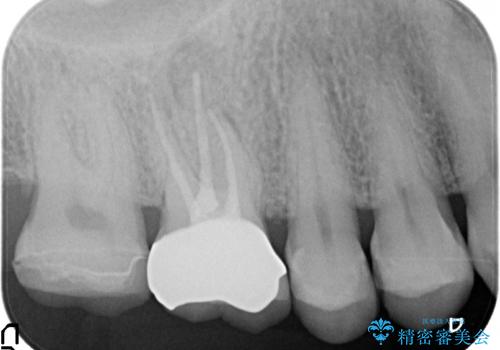

- 他院にて右上6の神経が死んでいるため根管治療が必要だと言われ当院にいらっしゃった方の症例です。

X線上で根尖病変を認めたため根管治療を行い、その後オールセラミッククラウンによる補綴を行いました